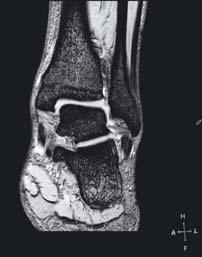

zwyrodnieniowa stawu skokowo-goleniowego

Staw skokowy dolny